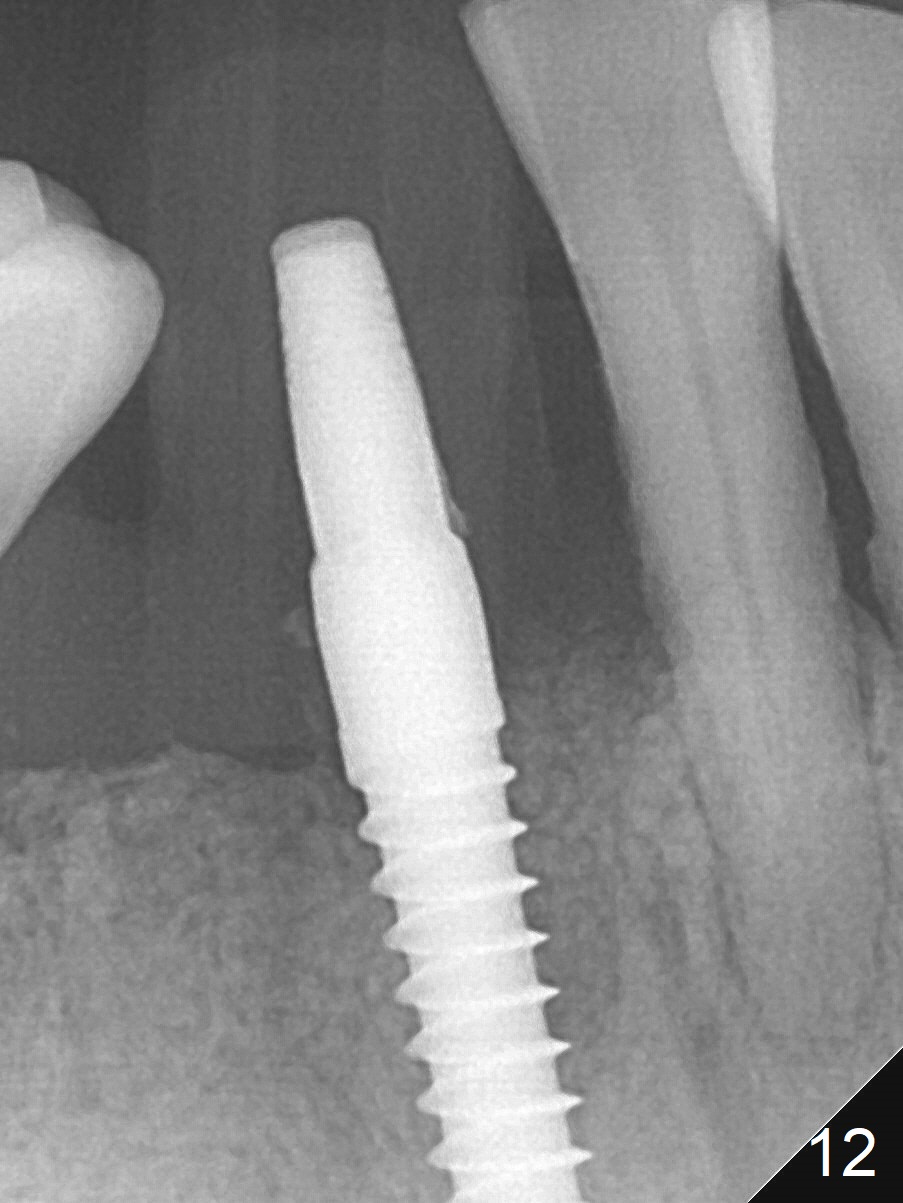

A 3x16(2) mm 1-piece implant is being placed as distal as possible (Fig.5 with 45 Ncm) with the mesial gap (*). The latter is filled with bone graft (Fig.6 *). The implant threads are not exposed 3 months 1 week postop (Fig.12).